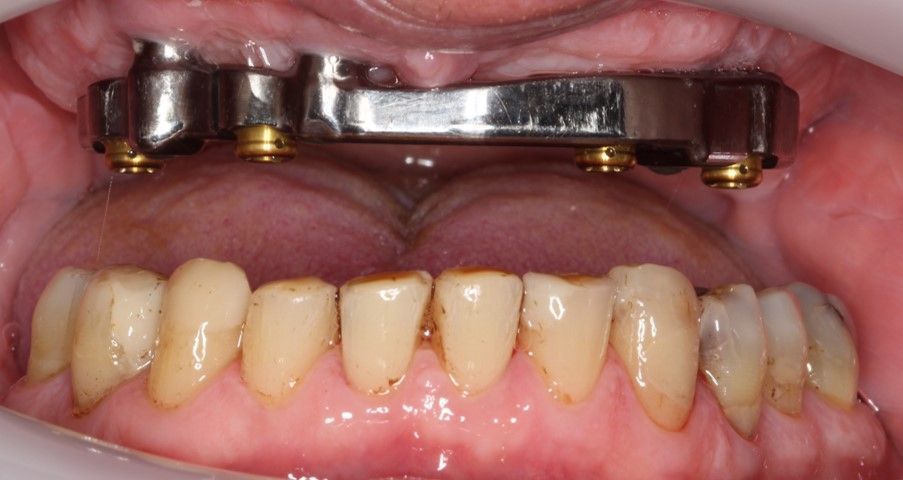

FULL ARCH BAR RETAINED

Four dental implants placed in the mandible and maxilla can be linked with a precision milled bar to retain and support an overdenture. This has the advantage of being removable for cleaning and maintenance.